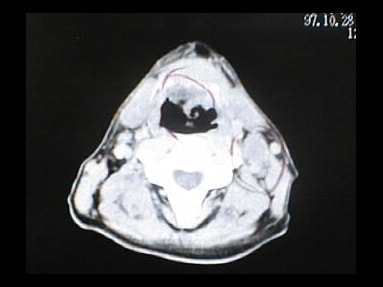

末期がん宣告時と末期がん消滅時の診断画像比較

ここでは、末期がんと宣告された時のCT&MRI画像と、その約3か月後の末期がん消滅時の画像を比較して頂けます。(写真左が「末期がん宣告時の画像」、写真右が「末期がん消滅後の画像」)

MRI画像比較

入院当時MRI画像①

入院3か月後癌消滅MRI画像①

入院当時MRI画像②

入院3か月後癌消滅MRI画像②